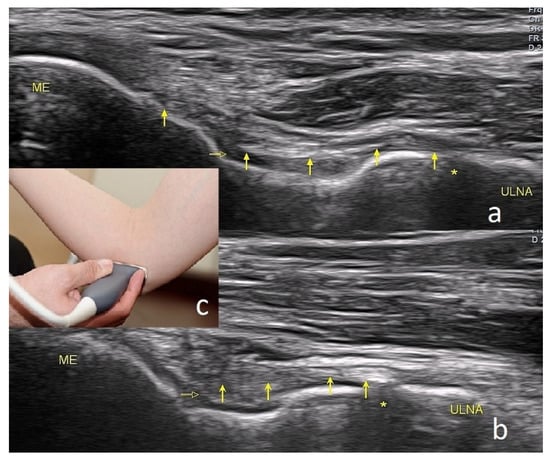

4.2. Snapping Triceps with Ulnar Neuritis